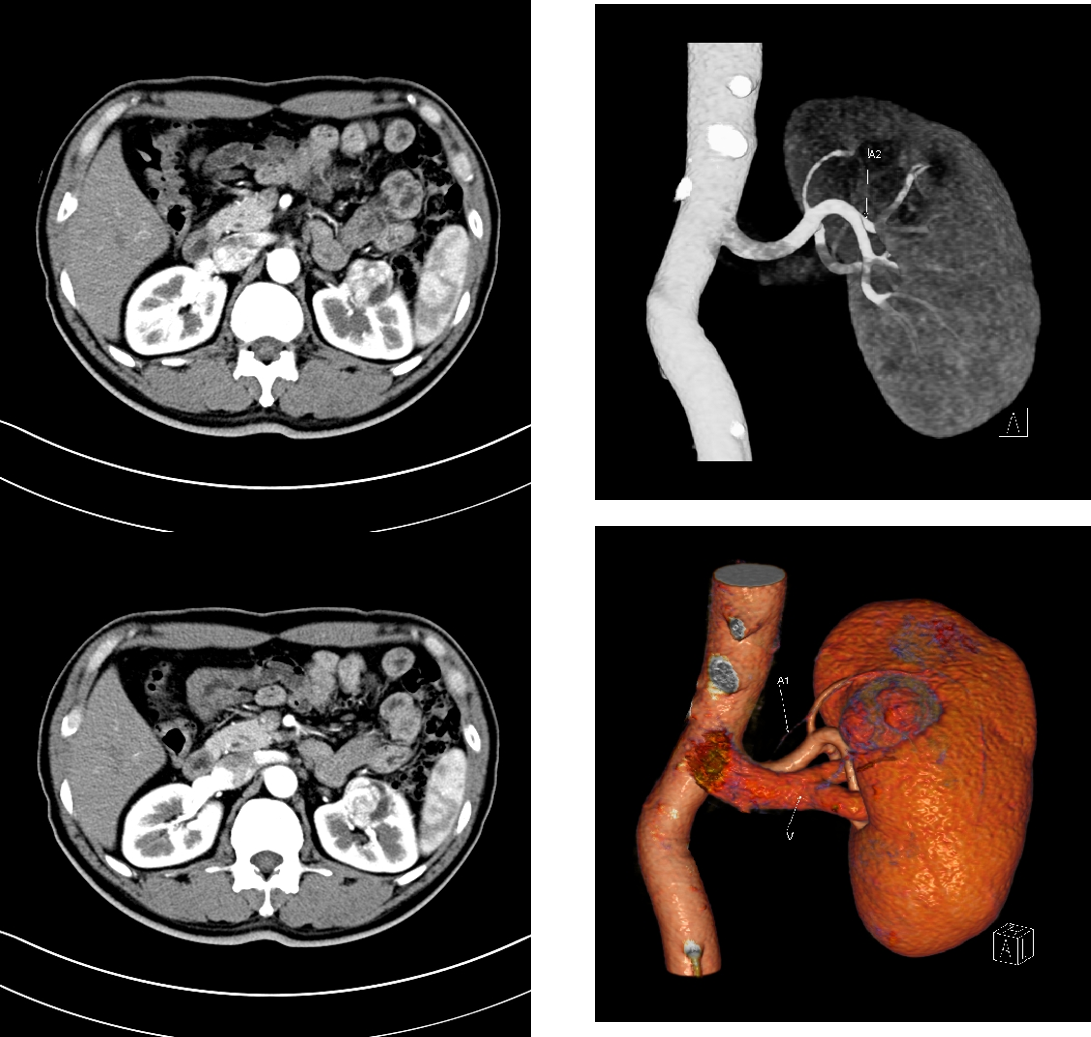

手术笔记:1例10cm左肾肿瘤的手术总结_肾肿瘤_肾肿瘤治疗方式 - 好